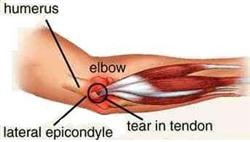

Colloquially referred to as tennis elbow because tennis players often suffer from the complaint, external humeral epicondylitis (or radio-humeral epicondylitis) is an ailment often affecting housewives, bricklayers, carpenters, and others who have repeated elbow movements. Owing to the strain over a long period of time, tendons and soft tissues surrounding the elbow joints can become inflamed or torn. Because of the friction, the periosteum can also be damaged, resulting in periostitis.

Colloquially referred to as tennis elbow because tennis players often suffer from the complaint, external humeral epicondylitis (or radio-humeral epicondylitis) is an ailment often affecting housewives, bricklayers, carpenters, and others who have repeated elbow movements. Owing to the strain over a long period of time, tendons and soft tissues surrounding the elbow joints can become inflamed or torn. Because of the friction, the periosteum can also be damaged, resulting in periostitis.One of the main symptoms of the complaint includes pain in the outer elbow joint, which will radiate toward the outer forearm, resulting in a powerless grip. When using a screwdriver or drying with a towel, local pain will be intensified. There will be some swelling in the affected area. Pain will increase when it is pressed. To see whether you are suffering from tennis elbow, you can carry out a test by rotating your arm and bending your wrist. The whole process is to straighten you elbow joint, bend your wrist and then rotate the arm clockwise, if the pain in your elbow increases, that means you may have tennis elbow.

Our clinic has adopted a combination treatment of acupuncture and herbal medicine to assist patients who are suffering from tennis elbow. It aims to achieve fast pain relief and restore the functions of the elbow joints by eliminating inflammation and promoting healing of the tears.